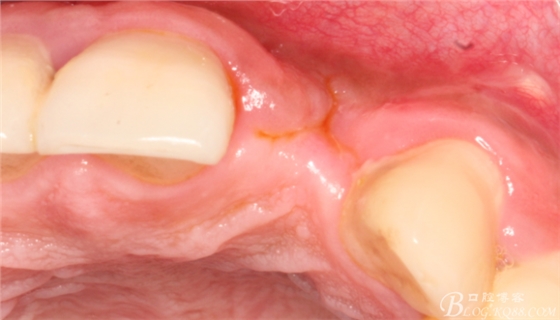

4個(gè)月后,唇側(cè)豐滿度尚可,與鄰牙之間齦乳頭完整。

保留齦乳頭翻小瓣。

翻開后驚喜的發(fā)現(xiàn),術(shù)區(qū)成骨非常好,去除部分骨才暴露那顆長鈦釘。